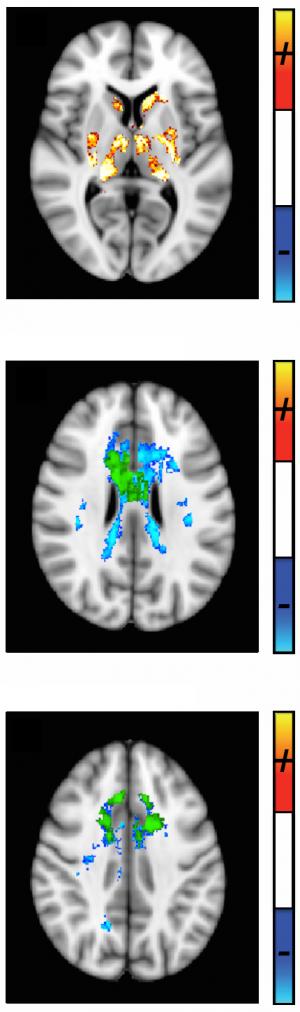

„În cercetarea din scleroza multiplă există ceva numit paradoxul clinico-radiologic. Când realizezi un RMN convenţional (Imagistică prin Rezonanţă Magnetică Nucleară) acestor pacienţi, vizualizezi leziuni la nivelul creierului foarte clar, însă numărul şi volumul acestor leziuni nu sunt corelate cu dizabilităţile pacienţilor. Acest paradox a fost recunoscut de când RMN-ul a fost introdus în practica clinică la începutul anilor 1980, iar în prezent este singura metodă imagistică prin care putem analiza scleroza multiplă”, afirmă Menon. „Cercetarea noastră oferă o metodă cantitativă care foloseşte secvenţe imagistice relativ convenţionale, dar cu o analiză inovativă a acestora. Această metodă demonstrează că există o pierdere considerabilă în zone obişnuite la toţi pacienţii cu scleroză multiplă, atât la nivelul substanţei albe, cât şi la nivelul structurilor cerebrale profunde – substanţa cenuşie. Aceste măsuri cantitative – ceea ce numim susceptibilitate cantitativă, sunt corelate cu simptomele bolii.”

Tehnica foloseşte un RMN Siemens 3T standard (T=tesla – n.tr.) ceea ce înseamnă că poate fi reprodusă în orice spital, folosind tehnica numită susceptibilitate cantitativă. Cercetătorii au cartografiat acest parametru al RMN la 25 de pacienţi cu scleroză multiplă recurent-remisivă şi cu sindrom clinic izolat (jumătate dintre cei diagnosticaţi cu sindrom clinic izolat vor fi diagnosticaţi cu scleroză multiplă) măsurând atât demineralizarea, cât şi depunerea de fier. Cincisprezece subiecţi control corelaţi cu vârsta şi sexul au fost, de asemenea, scanaţi. În timp ce leziunile cerebrale şi spinale vizualizate cu RMN-ul tind să apară si să dispară cu timpul, susceptibilitatea cantitativă vizualizează regiuni obişnuite de pierderi cerebrale la toţi pacienţii, pierderi care sunt corelate foarte bine cu scorul scării extinse a dizabilităţii (EDSS-Extended Disability Status Score) care este o metodă standard folosită în măsurarea progresiei sclerozei multiple, precum şi cu vârsta şi timpul scurs de la diagnostic.

„În mod semnificativ, la nivelul substanţei albe, chiar şi unde nu găsim nicio leziune, suntem capabili să măsurăm pierderile, folosind cartografierea prin susceptibilitate cantitativă, în aceeaşi zonă, la toţi pacienţii. Astfel, chiar şi în cele mai „precoce” stadii ale bolii când scorurile de dizabilitate sunt foarte mici sau când persoanele încă nu au fost diagnosticate cu scleroză multiplă, există deja o pierdere semnificativă”, adaugă Menon. Această descoperire ar putea avea implicaţii diagnostice şi prognostice importante, având în vedere că există medicamente disponibile care pot să încetinească sau să oprească progresia sclerozei multiple dacă sunt începute suficient de devreme.